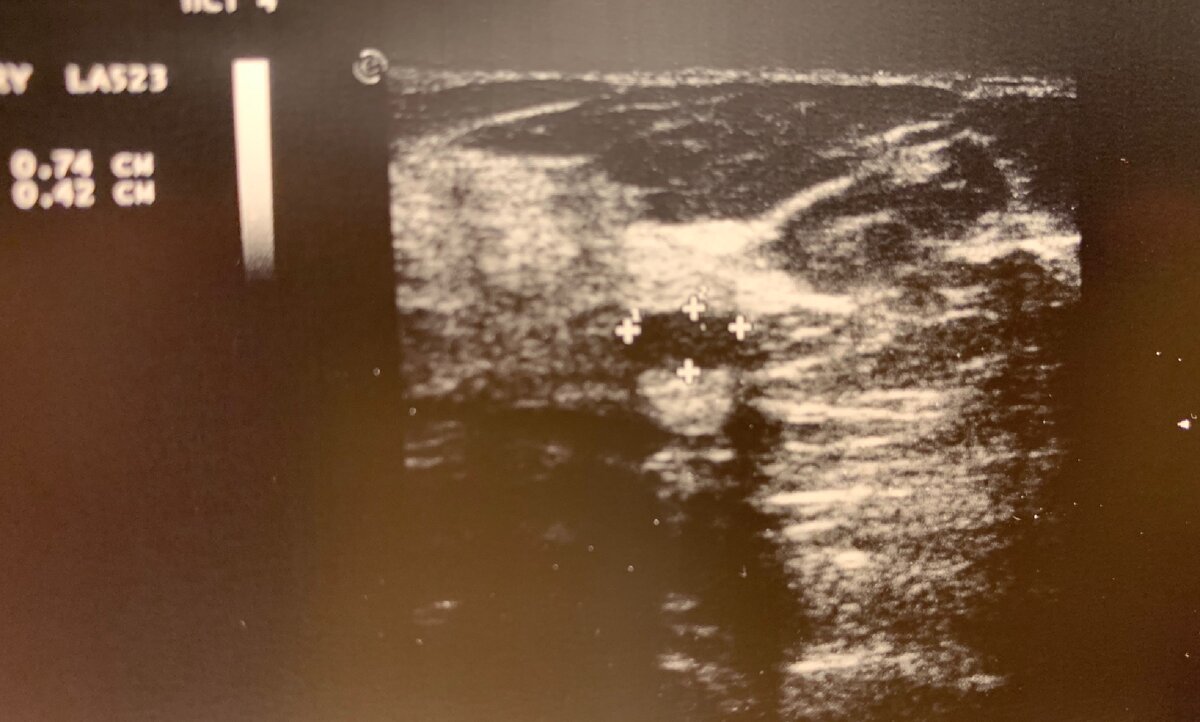

Как правило, гипоэхогенное образование с четким, ровным контуром, однородной структуры, горизонтальной ориентации, без измененного кровотока, легко смещаемое датчиком на УЗИ, является доброкачественной фиброаденомой.

УЗИ молочных желез- гипоэхогенное образование размером 7*4мм, фиброаденома?

Консервативного лечения данной опухоли не существует. Фиброаденомы размерами менее 20 мм, как правило, наблюдают и не подвергают хирургическому удалению, за исключением желания пациентки.